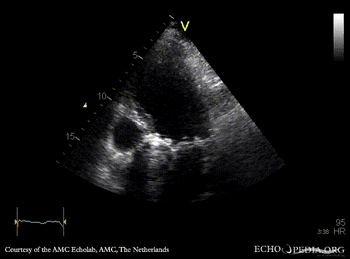

Rocking aortic valve prosthesis

A4CH: rocking aortic valve prosthesis A4CH: Color Doppler, severe aortic regurgitation